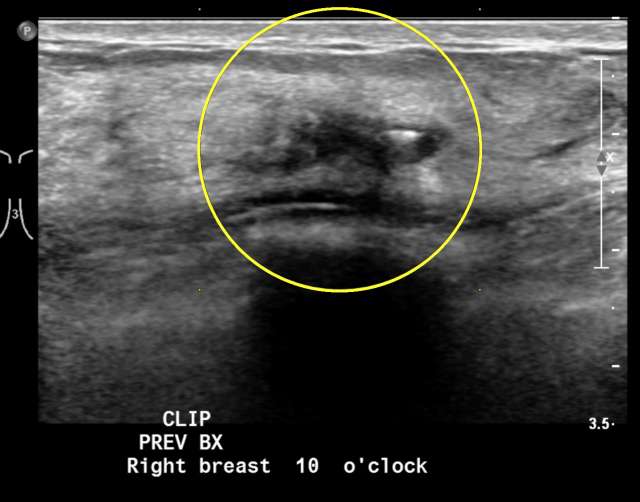

Case: Flat Epithelial Atypia Figure 2

Ultrasound image demonstrating a hypoechoic mass, which had been biopsied with pathology demonstrating FEA